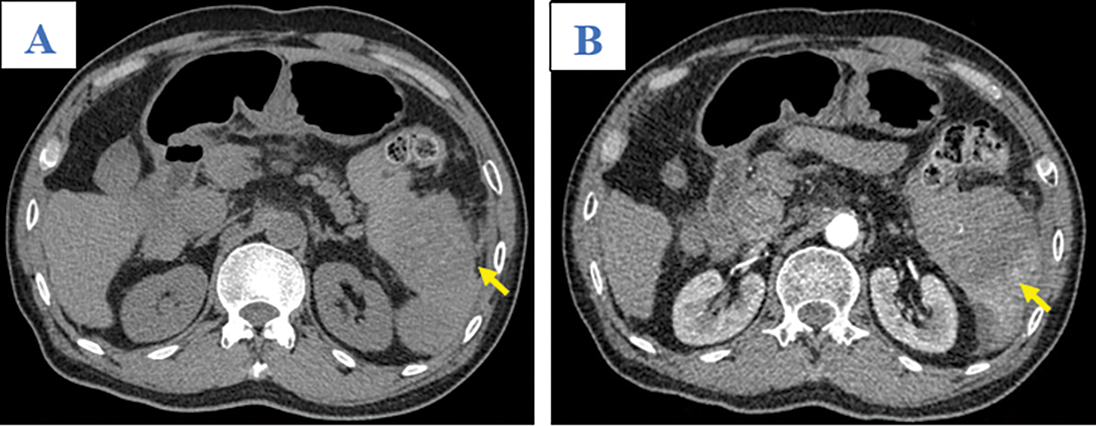

A 65-year-old man was admitted to our hospital complaining of fatigue and mild left-side abdominal pain without any history of recent trauma. He had a history of chronic hepatitis B infection for the past 6 years. Physical examination revealed a palpable mass below the left costal margin, which was defined as an enlarged spleen on abdominal ultrasound. Additionally, multiple nodules and masses were detected in the spleen and liver on ultrasonography. The patient was transferred to the oncology department with suspicion of metastatic disease with an unknown primary. Two days after admission, the patient developed severe acute abdominal pain, hypotension (80/50 mmHg), and tachycardia (105 beats per minute). Laboratory tests revealed a low hemoglobin (85 mg/dL), elevated alpha-fetoprotein (AFP; 8757 ng/mL), and elevated protein induced by vitamin K antagonist II (PIVKA-II; 23043.11 AU/mL). Bedside ultrasonography detected free intraperitoneal fluid with mixed internal echogenicity, suggesting hemoperitoneum. Therefore, urgent CECT was performed, which revealed a large quantity of hyperdense, free fluid in the pelvis and surrounding the inferior splenic pole, most consistent with hemoperitoneum (Fig. 1A). Multiple splenic masses were observed, with the largest in the inferior pole measuring 6 x 6 cm. The masses were hypodense on pre-contrast images (Fig. 1A) and demonstrated mild heterogeneous enhancement in the arterial phase (Fig. 1B), without gross change on portal venous (Fig. 1C) or delayed phase images (Fig. 1D). Discontinuity of the splenic capsule consistent with tumor laceration, was observed on post-contrast images without signs of active bleeding (Figs. 1C and 1D). In addition, multiple hepatic masses were observed, which were hypodense on pre-contrast images, and demonstrated marked peripheral hyperenhancement in the arterial phase, and non-peripheral washout in the portal venous and delayed phase images (Figs. 2A–2C). Right anterior portal vein thrombosis (Fig. 2D) was also identified. Multiple enlarged lymph nodes were observed in the hepatic hilum and paraaortic space, in addition to osteolytic lesions in the fourth and eighth thoracic vertebral bodies. The patient was diagnosed with hemoperitoneum due to presumed ruptured splenic metastasis, and an emergency splenectomy was performed. A liter of blood in the abdomen and a lacerated splenic mass were found on surgical exploration. Histopathology revealed a solid tumor with a well-defined margin between the tumor and the splenic parenchyma (Fig. 3A). The tumor cells were arranged in a trabecular pattern, with prominent nucleoli and hyperchromatism (Fig. 3B). Immunohistochemically, the neoplastic cells revealed solid and diffuse positivity for the hepatic marker hepatocyte paraffin 1 (HEPAR-1), indicating an HCC origin (Fig. 3C). The patient was diagnosed with Grade 2 HCC, with splenic and bone metastases, and metastatic abdominal lymphadenopathy. The patient was treated with targeted therapy. Finally, this patient was lost to follow-up.

Figure 1: Axial abdominal CT in the pre-contrast (A), Arterial (B), Venous (C), and Late phases (D). This mass presented as mildly hypodense in the pre-contrast phase (A; arrow) and with heterogeneous enhancement, without washout, on the arterial, venous, and late phases (B–D; yellow arrows). A tumor laceration was identified on the splenic capsule (C and D; white arrows) with the presence of hemoperitoneum (asterisk) but no observation of active bleeding